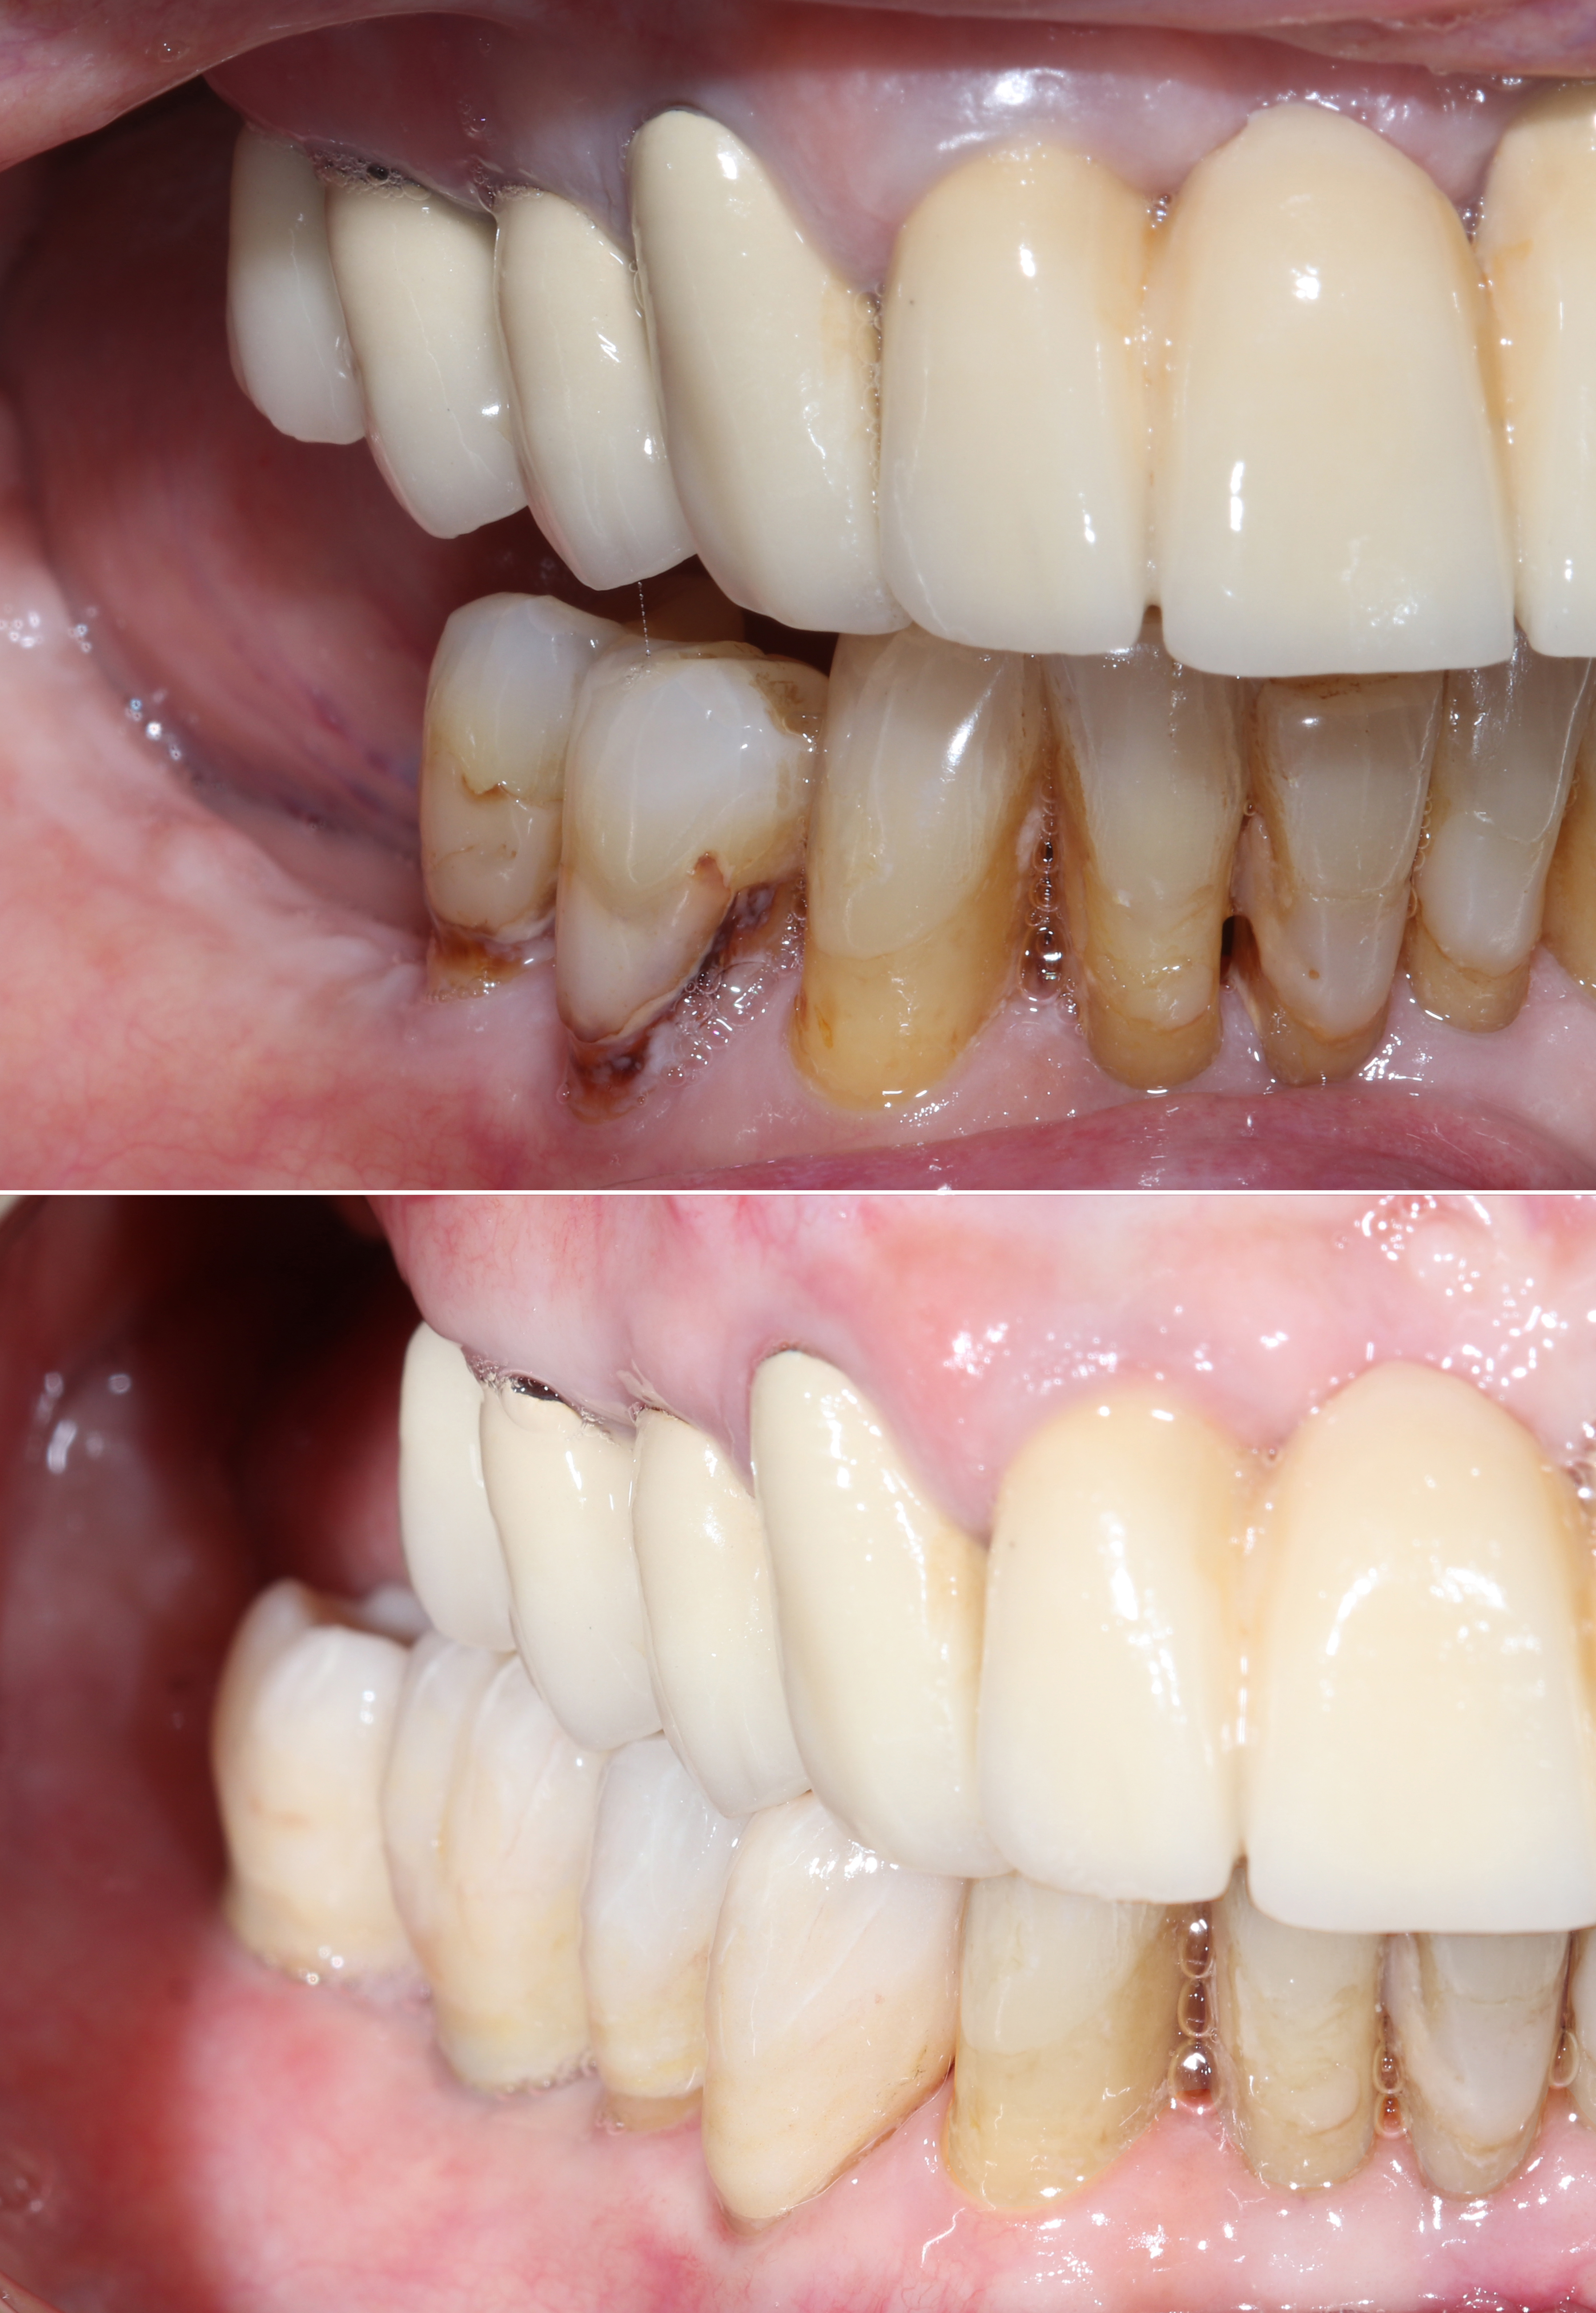

Αρχική κατάσταση - Χαμόγελο και πρόσθια άποψη

Αρχική κατάσταση - Πλάγια άποψη

Η κλινική εξέταση έδειξε επαρκή μαλακά μόρια και ικανοποιητικό προσθετικό χώρο με τα δόντια του αντίστοιχου φραγμού. Παρατηρήθηκαν επίσης εκτεταμένες εμφράξεις και τερηδόνες στα δύο δόντια μπροστά από το κενό, γεγονός που οδήγησε στην απόφαση για αποκατάστασή τους με ολόκεραμικες στεφάνες ζιρκονίου.

Τελική προσθετική αποκατάσταση

Μετά την επιτυχή οστεοενσωμάτωση, προχωρήσαμε σε ψηφιακή αποτύπωση με ενδοστοματικό σαρωτή και στην κατασκευή:

• Ακίνητης ολοκεραμικής γέφυρας ζιρκονίου δύο τεμαχίων επάνω στα εμφυτεύματα

• Δύο στεφανών ζιρκονίου στους παρακείμενους προγομφίους

Η τελική αποκατάσταση προσέφερε φυσική αισθητική, σταθερότητα και αποκατάσταση πλήρους μασητικής λειτουργίας, βελτιώνοντας ουσιαστικά την ποιότητα ζωής της ασθενούς.